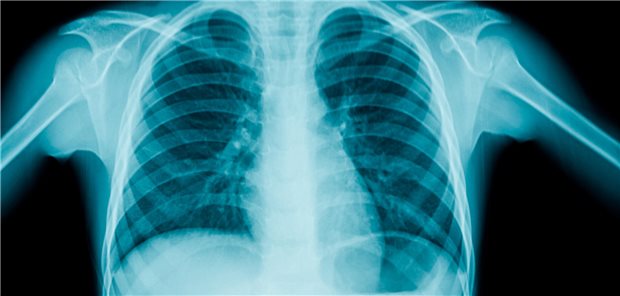

Pneumonie bei Kindern ausschließen: Auf das Röntgenbild ist offenbar Verlass